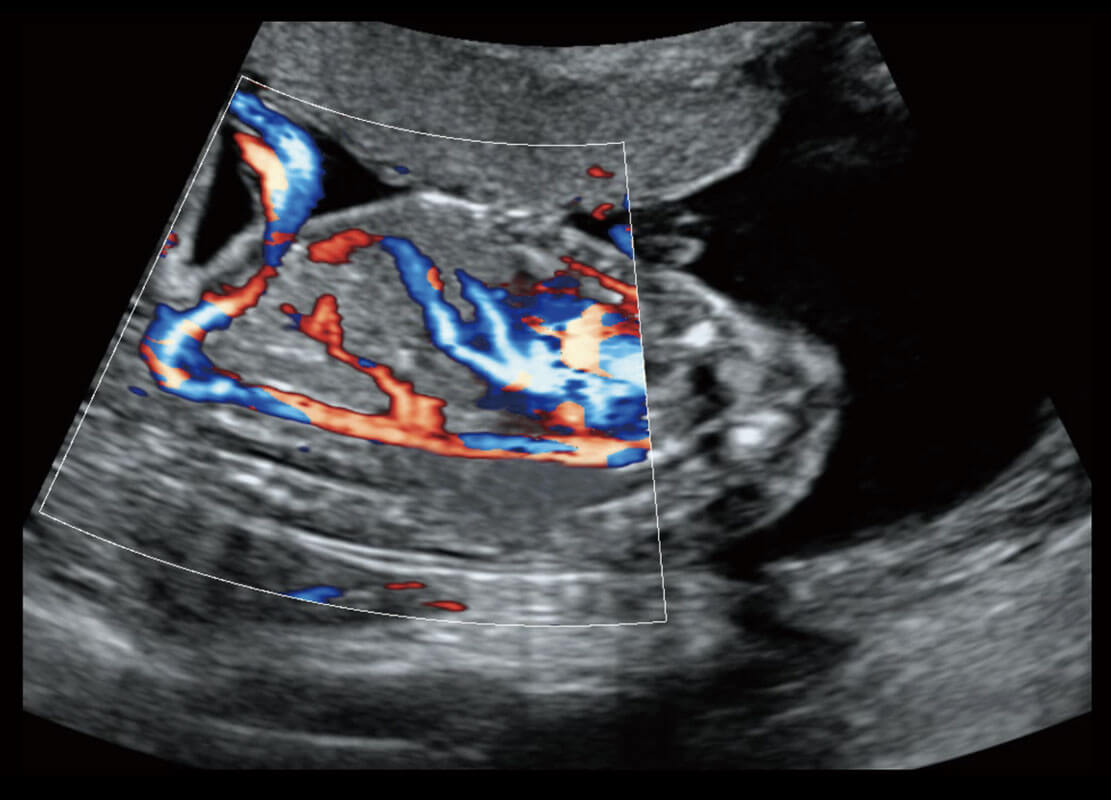

胎心筛查

P60搭载一系列胎儿心脏成像技术,实现精细的胎儿心脏评估。

• 四腔心血流